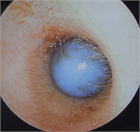

1. 耳閉感を伴う疾患は様々で、患者の訴えも「耳がつまる」以外に「耳がふさがった感じ」「耳の違和感」「音が反響する」「水が入ったような」など多様であるため、初診時の丁寧な問診が重要である(推奨度1)

1. 異物など除去により症状が消失するケースを除き、聴覚検査は診断に必須である(推奨度1)

1. 耳閉感を訴えている症例の中には、耳以外の疾患が原因の場合がある。特に脳血管疾患、腫瘍性疾患など生命予後を左右する鑑別疾患の可能性を想定した場合には、積極的に画像検査を施行する(推奨度1)